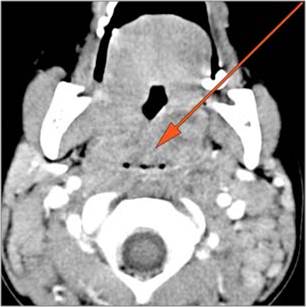

30-year old male with left facial swelling and tenderness mainly in the submandibular space. Primary clinical suspicion was an odontogenic infection.Exam

CT: Contrast- enhanced CT of the maxillofacial region and neck and related anatomy with images obtained in the balanced or venous vascular phase to ensure optimal visualization of both arterial and venous structures as well as possible reactive changes around infected collections. 0.5-3.0 mm thick sections were obtained in the axial plane and reformatted 3D and/or in the coronal and sagittal planes and viewed inter actively in 3 dimensions at the computer work station.